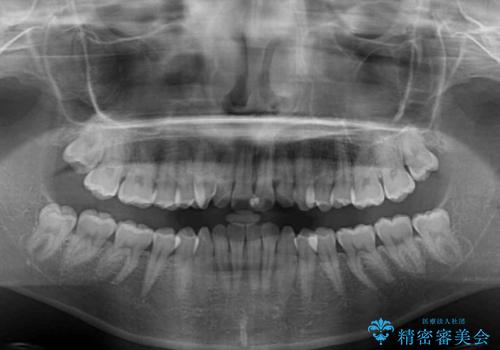

- 前歯のデコボコと下の前歯が隠れてしまう咬み合わせを気にして来院された患者様です。

インビザラインによる上下歯列の拡大と、IPR(歯と歯の間を削る)にるスペースの獲得により、口元のデコボコとディープバイトを改善することとしました。